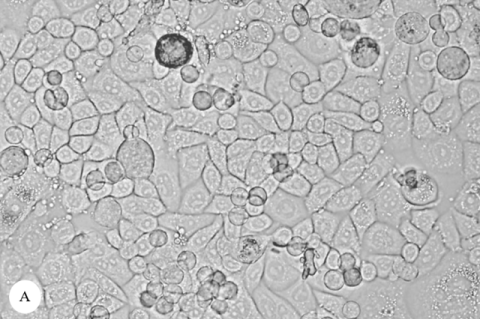

Morphological changes in MCF-7 cells. A: Non-cytotoxic MCF-7 cells (control). B: MCF-7 cells treated with methanolic G. elegans twig extract at 25 μg/mL showing significant cell death and morphological alterations